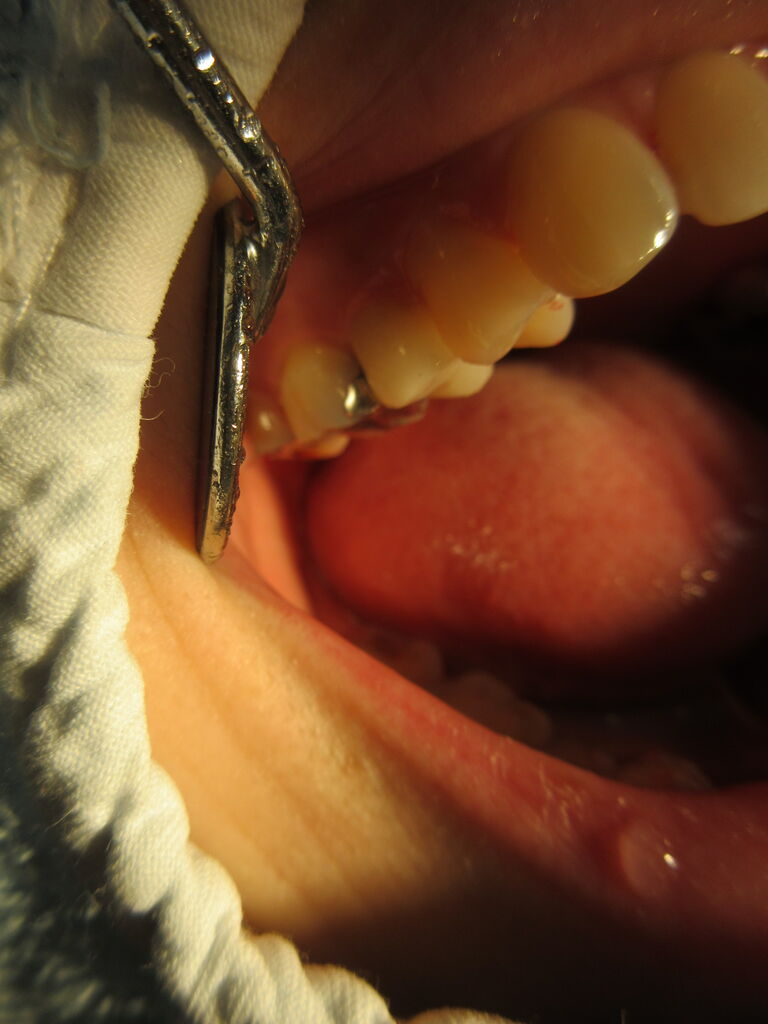

上顎右側小臼歯部にオールセラミックを装着。